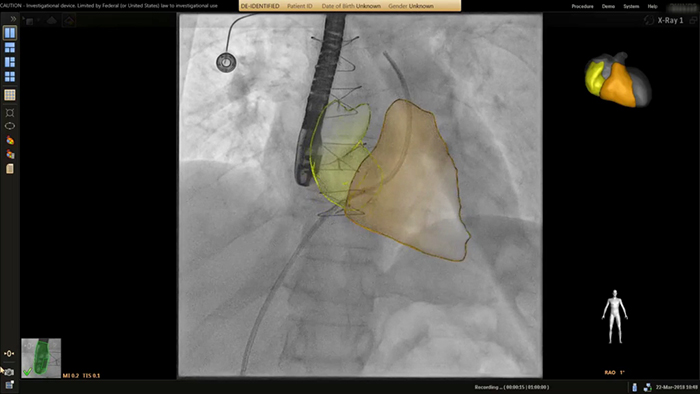

Wykonywanie zabiegu wszczepiania stentu w ramach leczenia zwężenia cieśni aorty pod kontrolą obrazu z użyciem systemu VesselNavigator

Prowadzenie pod kontrolą obrazowania w czasie rzeczywistym z użyciem aplikacji SmartCT